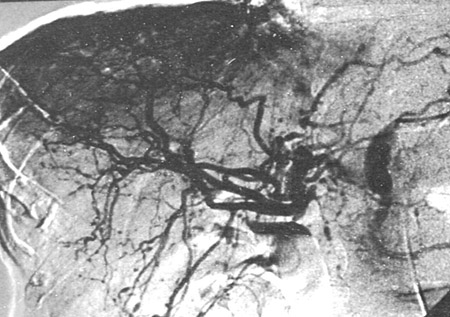

A angiografia convencional é a modalidade de exame de imagem de escolha e deve ser realizada caso haja suspeita clínica de PAN. A sensibilidade relatada é de 89%. A especificidade é de 90% quando realizada em pacientes com suspeita de vasculite.[40] Achados clássicos incluem pequenos aneurismas múltiplos, ectasia vascular e lesões oclusivas focais em vasos de tamanho médio, mais tipicamente nas artérias renais e mesentéricas.

A PAN não afeta os pulmões, mas a radiografia torácica pode ser útil em descartar outras doenças, como outras vasculites que podem afetar os pulmões, e excluir infecção.[Figure caption and citation for the preceding image starts]: Angiografia renal mostrando aneurismas, uma característica clássica de poliarterite nodosa (PAN)Do acervo do Dr Raashid Luqmani [Citation ends].

[Figure caption and citation for the preceding image starts]: Angiografia renal mostrando aneurismas e microaneurismasDo acervo do Dr Loic Guillevin [Citation ends].